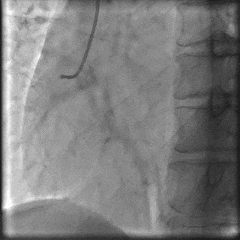

术前冠脉造影:

术前冠脉功能学全面评估:

▶IMR:24;CFR:2.5;FFR:0.76(+)。

术后冠脉造影:

术后即刻冠脉功能学全面评估:

▶IMR:18;CFR:3.2;FFR:0.89。